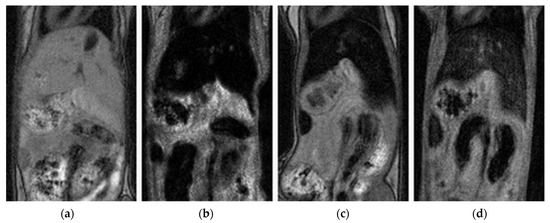

3.6. In Vivo Study